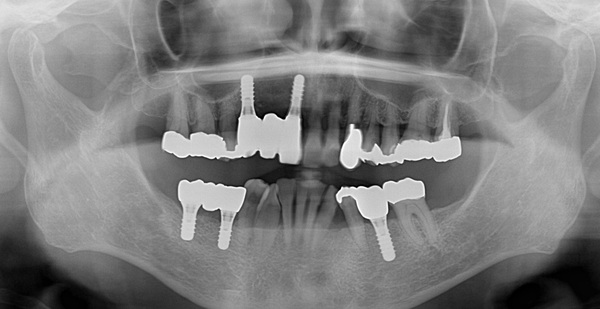

こちらがインプラント終了後のレントゲン写真になります。

無事に計画通り5本のインプラントが入りました。